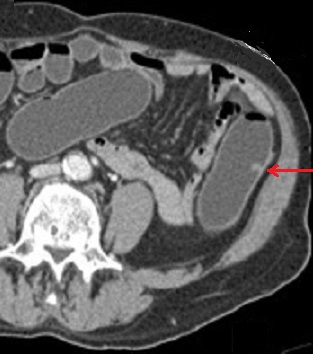

certaine cas de enterite inflammatoire compliquee . - Image

radiologique d'une coloscanner a

l'eau c'est la technique TDM avec une opacification du

colon a l'eau tiede ( comme une lavement baryte ) a l'aide

une sonde rectale . L'exploration et les exposes represence

apres distension colique a l'eau tiede avec injection de

contrast iode hydrosoluble

par voie intraveineuse :

Image d'une polyp du colon (

fleche rouge ) . Colos scanner a eau en coupe axiale

. Cette technique peu elimine des polyps de plus de

7mm |